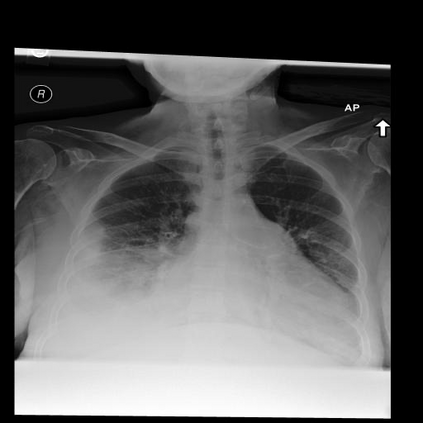

In this study, we aim to initiate the development of Radiology Foundation Model, termed as RadFM.We consider the construction of foundational models from the perspectives of data, model design, and evaluation thoroughly. Our contribution can be concluded as follows: (i), we construct a large-scale Medical Multi-modal Dataset, MedMD, consisting of 16M 2D and 3D medical scans. To the best of our knowledge, this is the first multi-modal dataset containing 3D medical scans. (ii), We propose an architecture that enables visually conditioned generative pre-training, allowing for the integration of text input interleaved with 2D or 3D medical scans to generate response for diverse radiologic tasks. The model was initially pre-trained on MedMD and subsequently domain-specific fine-tuned on RadMD, a radiologic cleaned version of MedMD, containing 3M radiologic visual-language pairs. (iii), we propose a new evaluation benchmark that comprises five tasks, aiming to comprehensively assess the capability of foundation models in handling practical clinical problems. Our experimental results confirm that RadFM significantly outperforms existing multi-modal foundation models. The codes, data, and model checkpoint will all be made publicly available to promote further research and development in the field.